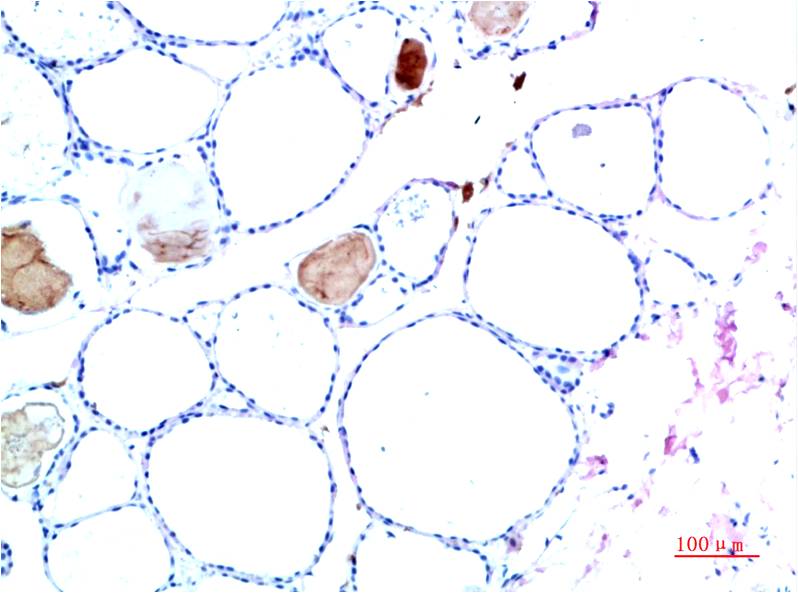

TTR Mouse Monoclonal Antibody(10H2)

Catalog NO.:BE3694

Applications :WB, IHC

Reactivity :H

Recommended dilutions: WB 1:1,000-2,000 IHC 1:100-200